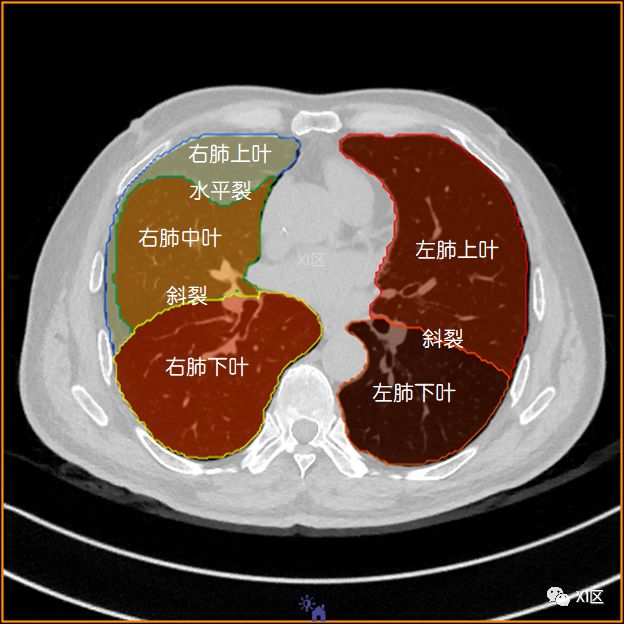

肺的分叶

左肺借斜裂成上、下两叶;右肺借斜裂和水平裂成上、中和下叶三叶。

横断位

肺的断层分段示意图

在进行肺的分段时,可以上下观察浏览,沿着相应气管的走形可以更容易准确地进行分段。